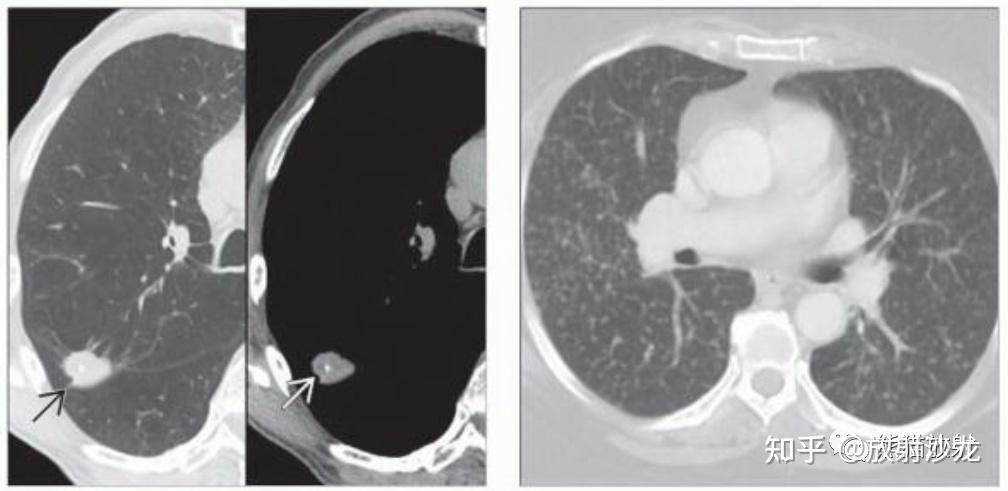

肺弥漫性浸润腺癌,与间质性肺结核及粟粒型肺结核的鉴别—潘军平

右肺上叶肿瘤

右肺上叶恶性肿瘤